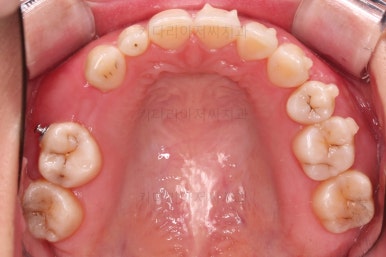

초진 시 입안의 모습인데요.

왜 그런지 비밀이 풀리는 것 같죠?

윗니는 한 쪽이 치아 2개가 결손이면서 유치가 하나 남아있고요.

아랫니는 한 쪽은 1개, 반대편은 2개 치아가 결손이었습니다.

도합 5개의 치아가 결손이었는데요.

결손 위치의 갯수가 위아래 좌우 다 달라서 중앙선이 맞을래야 맞을 수가 없는 상황이었죠.

결손치아 주위 치아들은 쓰러지고 비틀어져 있어서 장기적으로 좋지 못한 상황이었고요.

좀 더 디테일하게 윗니 작은 앞니 1개가 왜소치아라서 치아 크기도 맞지 않은 상황이었습니다.